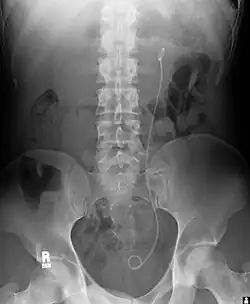

- ureterale, suprapubische oder urethrale Katheterisierung, z. B. Doppel-J-Katheter (Ureterstent, pigtail-Katheter)